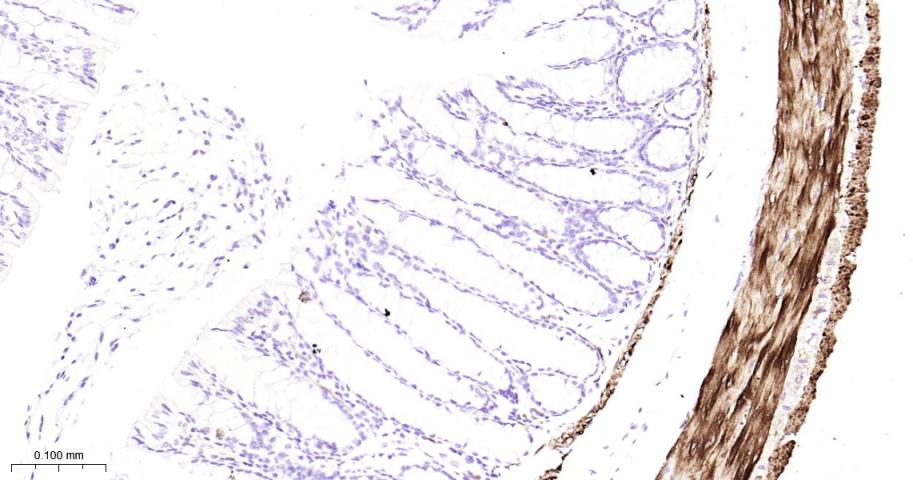

Paraformaldehyde-fixed, paraffin embedded Mouse Colon; Antigen retrieval by boiling in sodium citrate buffer (pH6.0) for 15 min; Antibody incubation with Hsp27 Monoclonal Antibody, Unconjugated(bsm-52757R) at 1:200 overnight at 4°C, followed by conjugation to the bs-0295G-HRP and DAB (C-0010) staining.

Paraformaldehyde-fixed, paraffin embedded Rat Colon; Antigen retrieval by boiling in sodium citrate buffer (pH6.0) for 15 min; Antibody incubation with Hsp27 Monoclonal Antibody, Unconjugated(bsm-52757R) at 1:200 overnight at 4°C, followed by conjugation to the bs-0295G-HRP and DAB (C-0010) staining.

Paraformaldehyde-fixed, paraffin embedded Human Colon; Antigen retrieval by boiling in sodium citrate buffer (pH6.0) for 15 min; Antibody incubation with Hsp27 Monoclonal Antibody, Unconjugated(bsm-52757R) at 1:200 overnight at 4°C, followed by conjugation to the bs-0295G-HRP and DAB (C-0010) staining.